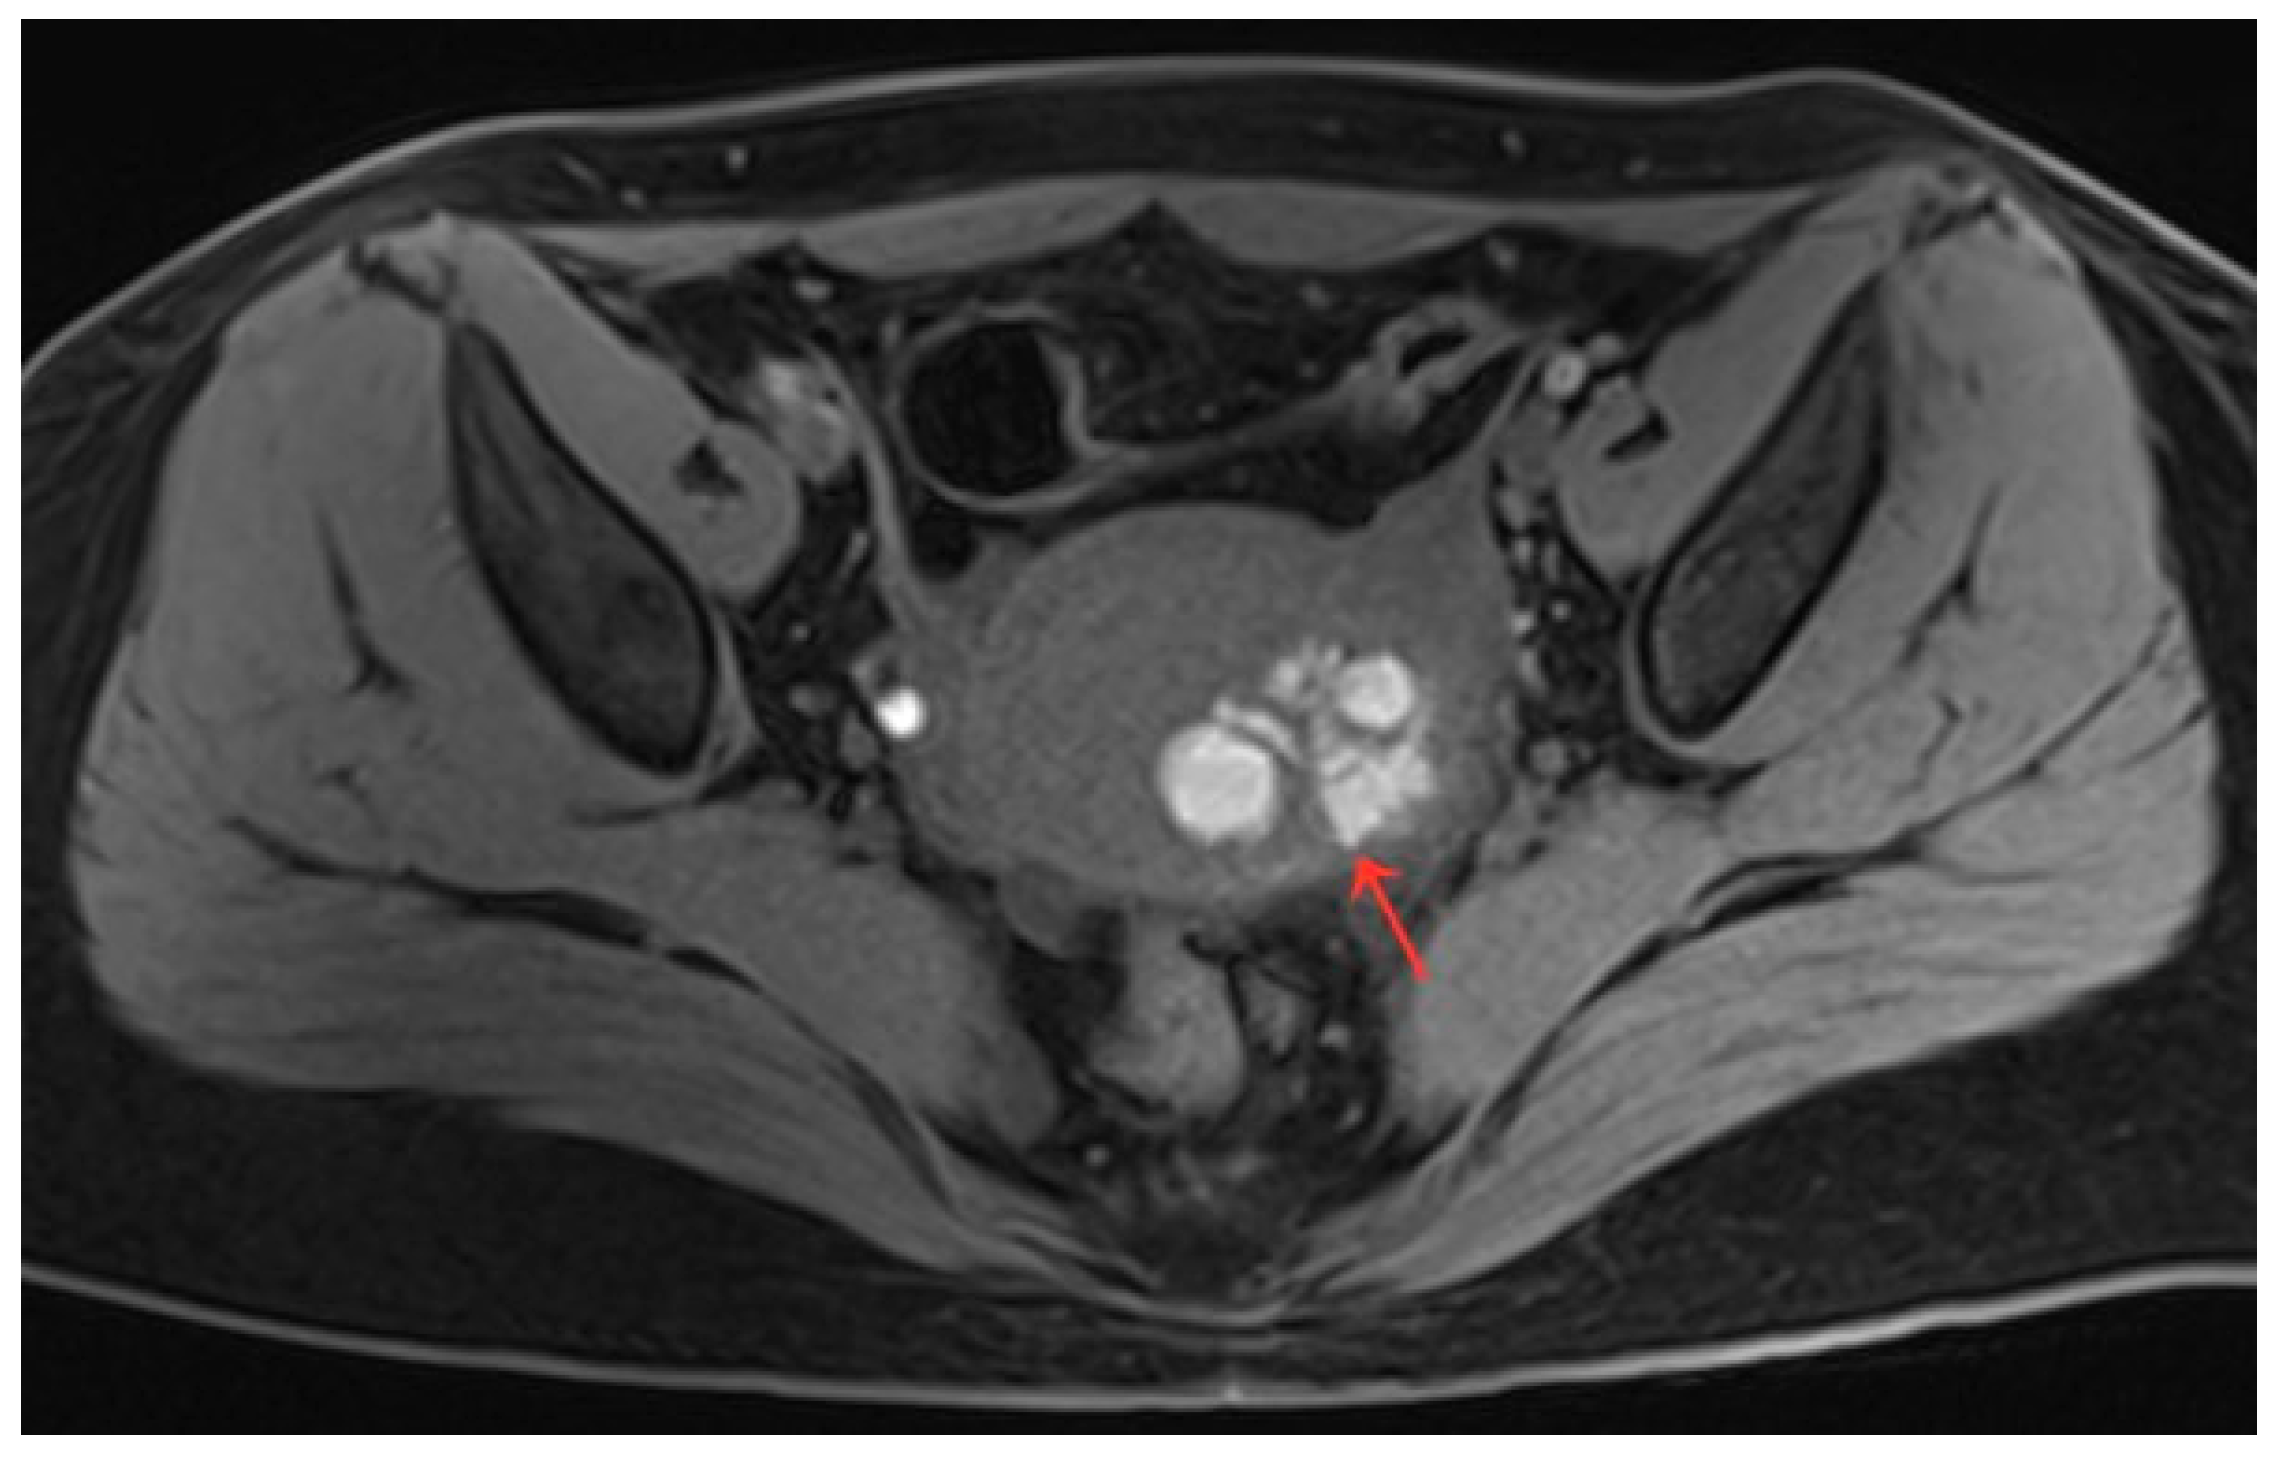

Figure 1.

(a–c) Pelvic MRI: sagittal TIWI sequence (a), sagittal T2WI fat suppression sequence (b), and axial T2WI non-fat suppression (c) showing a cystic lesion in the right posterior wall of the uterus with regular morphology, oval shape, and clear border (red arrows).